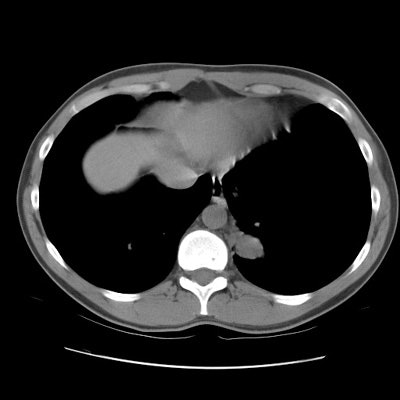

CT scan revealed a soft tissue mass in the left posterior-medial lung which had a branching tubular appearance. Some associated para-emphysematous changes were noted. (Click images to enlarge)